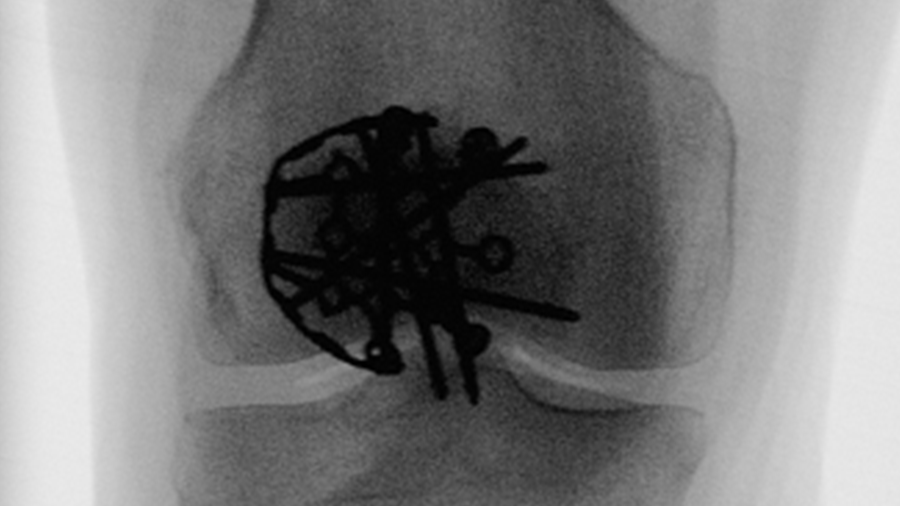

Locked lateral plating vs. tension band wiring in patella fractures

Investigating the biomechanical performance of the two methods used for fixation of simple and complex patella fractures.